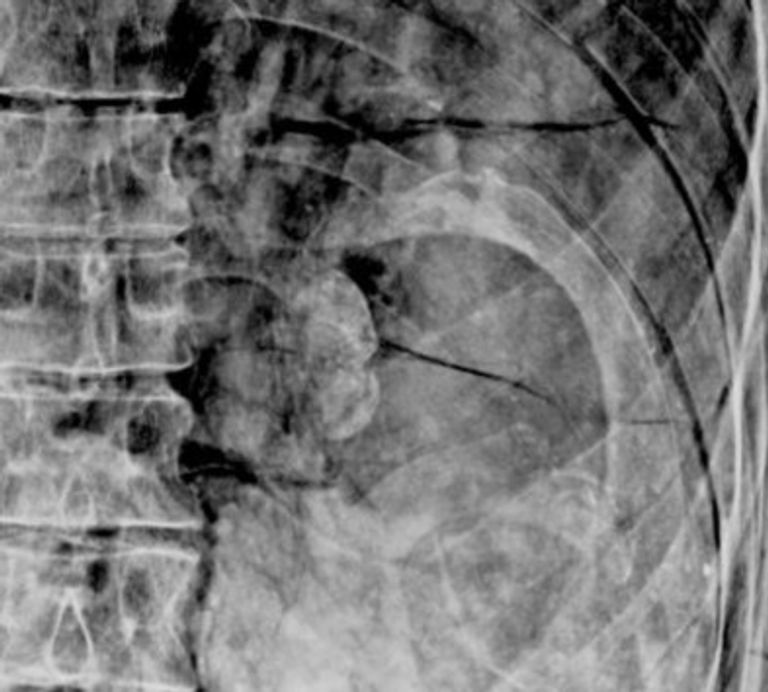

وفي دراسة نُشِرت تفاصيلها بدورية العلوم الأثرية في عام 2019، تم إخضاع المومياء للتصوير المقطعي والأشعة السينية التي كشفت عن إصابة صاحبها بآفات عظميّة صلبة متعددة البؤر تؤثر على العمود الفقري والورك الأيسر.

ورغم عدم استبعاد الباحثين سيناريو تغيّر الأنسجة بفعل عمليات التجفيف والتحنيط التي أجريت للمومياء ما ساهم في إحداث تشوهات بالتشريح المورفولوجي أدت لهذه الأعراض، لكنهم أكدوا أنَّ الاحتمال الأرجح هو إصابة صاحبها بالسل الذي أدّى إلى تلك التشوهات.